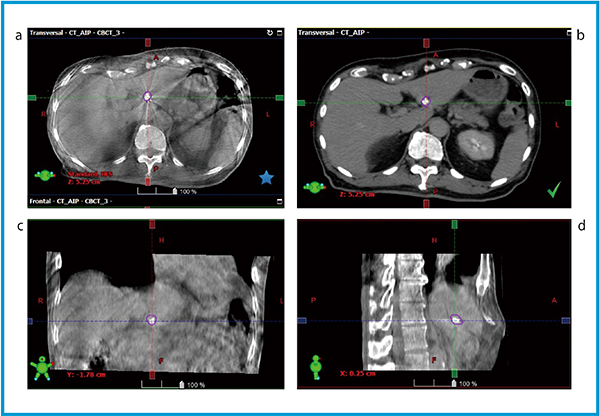

図2 放射線治療計画用CT画像とCBCT画像による金マーカーを用いた画像誘導放射線治療の例

放射線治療計画用CT画像(b)上に金マーカーの呼吸性移動を反映させた輪郭を作成し(○),位置照合に利用する(a,c,dはCBCT画像)。